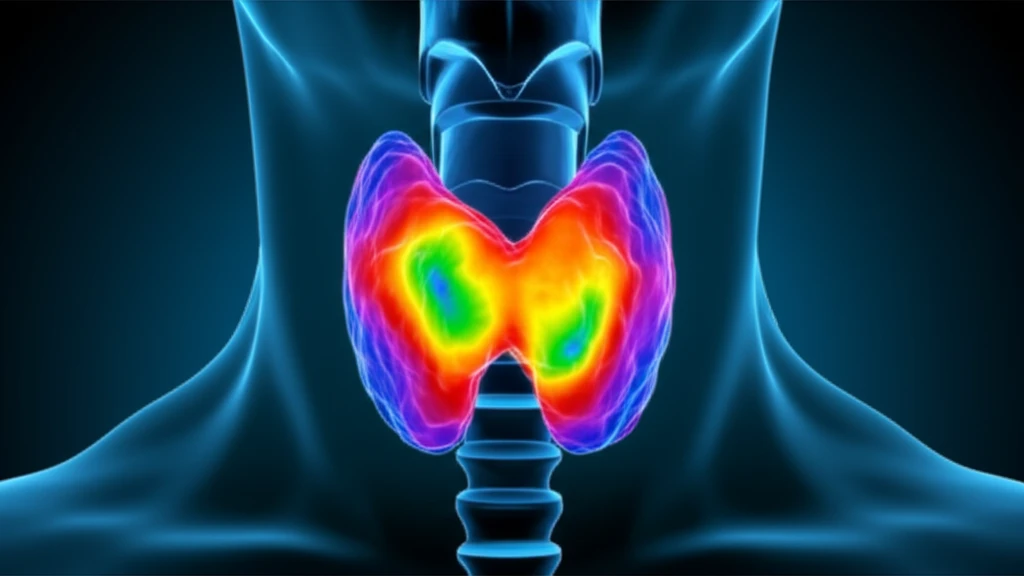

Thyroid nodules are common, affecting a significant portion of the population. While most are benign, the possibility of malignancy always looms, creating anxiety and diagnostic challenges. Current methods, like ultrasound and fine-needle aspiration (FNA) biopsies, have limitations in definitively ruling out cancer, leading to potential overtreatment and unnecessary surgeries.

Advanced imaging techniques offer promising solutions. Diffusion-Weighted Magnetic Resonance Imaging (DW-MRI) is emerging as a valuable tool for assessing thyroid nodules. DW-MRI measures the movement of water molecules within tissues, providing insights into cellular density and integrity – characteristics that differ significantly between benign and malignant tissues.

DW-MRI works by detecting how water molecules move within body tissues. In areas where cells are densely packed (like in tumors), water movement is restricted. This restriction is measured by the Apparent Diffusion Coefficient (ADC). Malignant tissues typically show lower ADC values compared to benign tissues because of their higher cellular density.